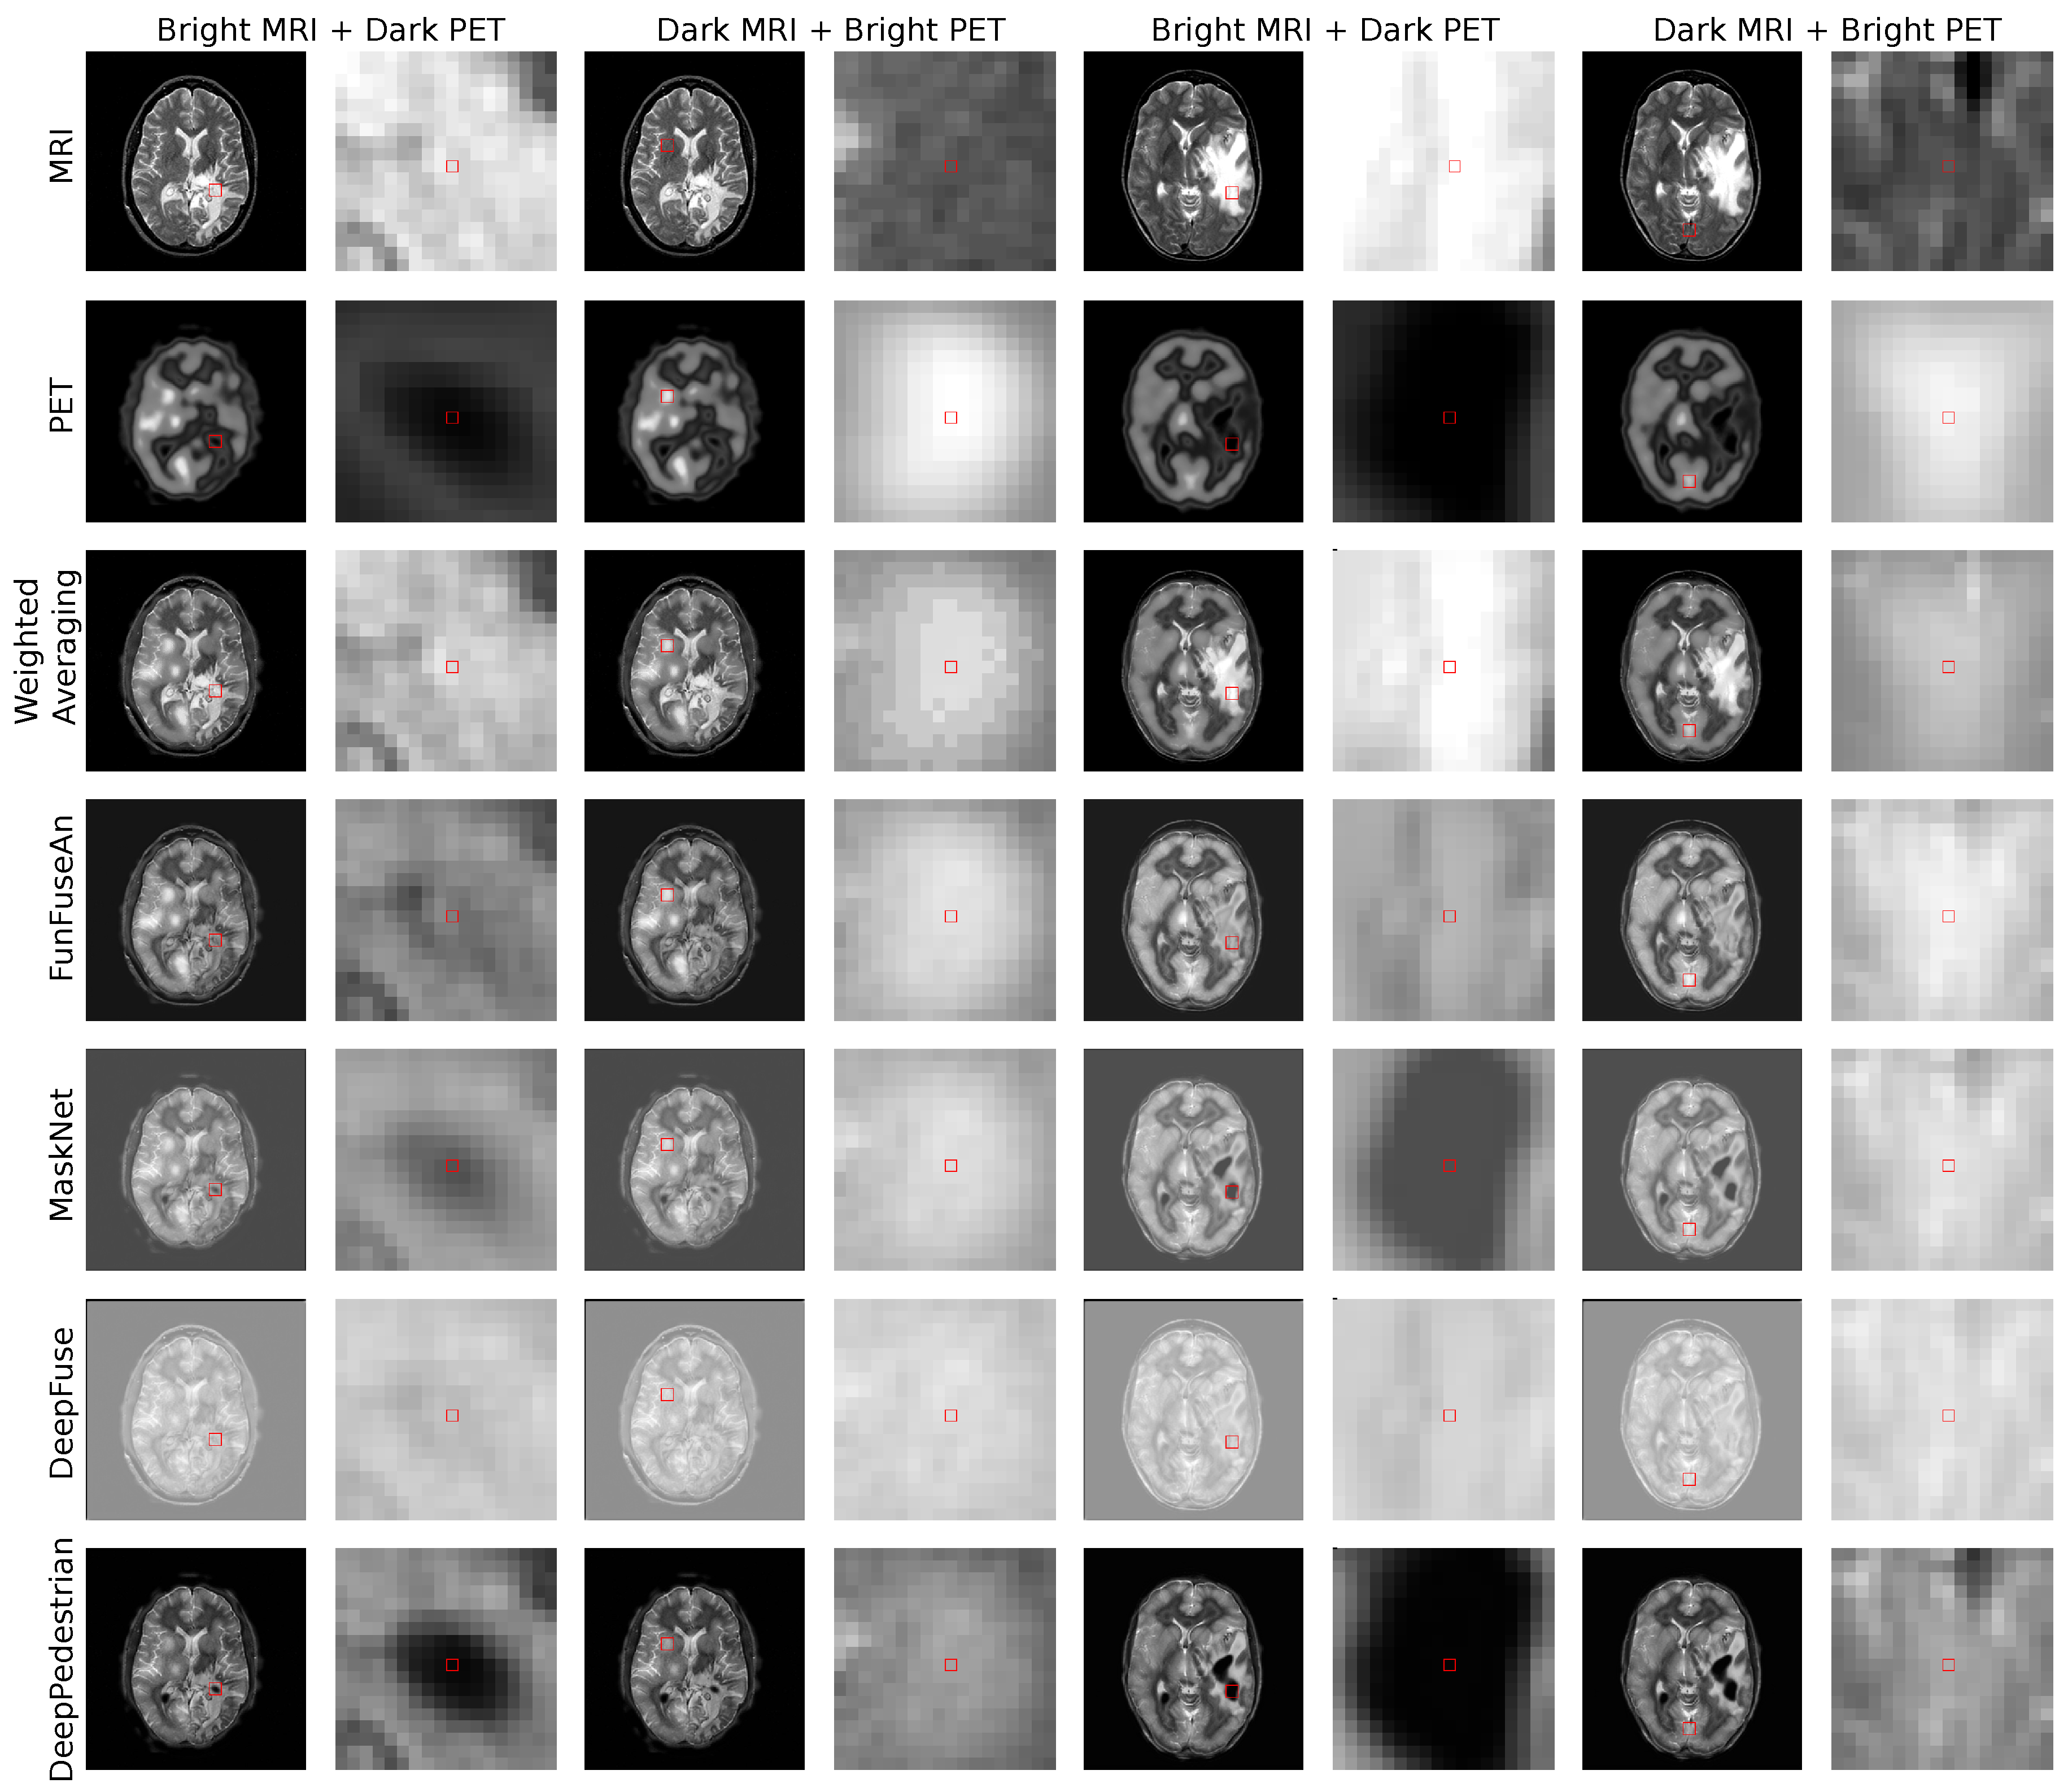

5.2. Clinical Test Examples

The clinical test examples were acquired from Harvard Whole Brain Atlas database [73] with the combination of MRI-T2 and PET/SPECT images from patients suffering from different types of glioma. The test examples were disjoint to the training dataset and the network has not seen such clinical pathology during its training. The first clinical MRI-PET image pair is shown in the first four columns of Figure 4. The scans are of a patient who was suffering from Anaplastic Astrocytoma, a rare and malignant brain lesion classified under the category of high-grade glioma. A lesion in the right and the left side of the brain is visible in the MRI image and has bright grayscale intensities. On the other hand, bright regions in the PET image convey normal blood flow while very dark regions suggest no blood flow in the necrotic tissues. In the second clinical MRI-PET image pair as shown in the last four columns in Figure 4, the patient had a long history of tobacco usage and was originally suffering from Metastatic Bronchogenic Carcinoma, which is a type of lung cancer. The patient began having headaches and the scans revealed brain metastases that occurred due to the spread of cancer cells present in the lungs to the brain resulting in the diagnosis of glioma. A lesion in the right side of the brain with bright features is visible in the MRI image while very dark PET features reveal no blood flow in the necrotic region.

• A fusion approach should assist clinicians in visualizing the extent of hyper dark PET regions resembling necrotic core with no blood flow being superimposed on the bright anatomical boundary of the whole tumor mass. This information is important for clinicians to estimate the extent up to which a tumor resection is required. For example, in the first and the fifth column of Figure 4, the principle pixel in this very dark PET region was chosen for visual analysis.

• A fusion approach should preserve the very bright PET features which convey high blood perfusion and normal metabolism in healthy brain tissues as it helps clinicians in visualizing the regions with high brain activity due to external stimuli at a particular time. For example, in the third and seventh column of Figure 4, the principal pixel in the bright PET region was chosen for visual analysis.

6.1. Fused Images

The fused images of the Weighted Averaging method as shown in the third row of Figure 4 gives very high weightage to the bright input intensities in the regions where intensities in the other modality are darker. Therefore, we can perceive a reproduction of features from relatively brighter regions of the MRI and PET images due to which Weighted Averaging method is unable to preserve the clinically important dark PET features related to the necrotic core but favorably preserves the bright PET features resembling healthy tissues. The fused images of the FunFuseAn as shown in the fourth row of Figure 4 are comparatively similar to the Weighted Averaging approach where it is not able to preserve the very dark PET features. However, the fused images from FunFuseAn look relatively dull compared to the fused images from Weighted Averaging since the FunFuseAn network mixes both MRI and PET features even though the boundary information about the necrotic region is lost.

The analysis of the fused images from MaskNet in the fifth row of Figure 4 shows a significant loss of anatomical edges from MRI such as the brain skull. However, contrary to Weighted Averaging and FunFuseAn, MaskNet preserved the PET features better in both the dark and bright regions resembling the necrotic core and healthy tissues, respectively. However, the dark PET features are slightly blurred due to changes in the overall brightness of the fused image. The fused image obtained from DeepFuse as shown in the sixth row of Figure 4 has an even higher shift in grayscale intensities due to which the method is unable to preserve the dark PET features even though the overall anatomical MRI structures are well preserved. The change in brightness can be explained by the fact that the L 2 M R I and L 2 P E T converged at higher loss values compared to other networks due to which the brightness component of SSIM was not properly optimized. Additionally, the architecture of DeepFuse network has been crafted for adding exposure to underexposed images by using the brightness component from each of the input image modalities and employ it to generate very bright fusion results. The fused image from DeepPedestrian as shown in the seventh row of Figure 4 clearly delineates the boundary of the necrotic core by preserving the very dark PET features, which is of high clinical significance for medical professionals. However, the anatomical edges from MRI are lost in the fused image which is also one of the main artifacts in the MaskNet network. Another important observation is that the bright PET features resembling healthy tissues appear to be not well preserved due to an overall brightness shift.

6.2. Guidance Images

In this section, we analyze the fusion methods with respect to its sensitivity to feature level changes in the input images by visualizing the Guidance MRI and Guidance PET images in Figure 5 and Guidance RGB images in Figure 6 for the two clinically relevant regions. We chose the first region as bright MRI with very dark PET features since it is the region that contains the necrotic core of glioma which clinicians are interested to operate for resection. The second region of interest has dark MRI with bright PET features resembling healthy tissues which is interesting for the visualization of high brain activity due to external stimuli. Ideally, a guidance MRI image should have low gradients meaning a fusion method should be less sensitive to changes in both dark and bright MRI regions.